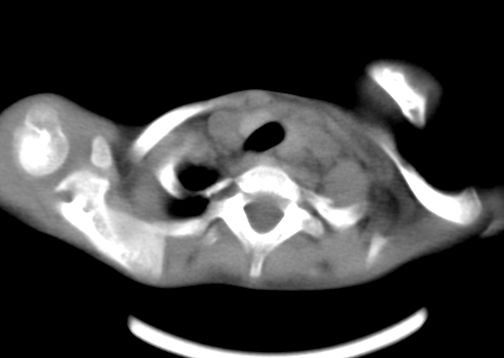

患儿 女 4岁,发热 咳嗽 胸透 考虑:左侧脓胸

左侧胸廓内见大量密实阴影,肺尖部尚有少量肺组织影,纵膈明显受压移位,肋骨未见明显受侵征象,虽然病人年龄较小,但如此大量的“积液”,还是要警惕,不同意一般感染,可结合穿刺脱落细胞学检查。

1)考虑左肺炎症感染。2)左侧大量胸腔积液。

1)考虑左肺炎症感染。2)未经穿刺只能定左侧大量胸腔积液。

左侧张力性大量胸腔积液压迫性肺不张、感染;建议治疗后复查。